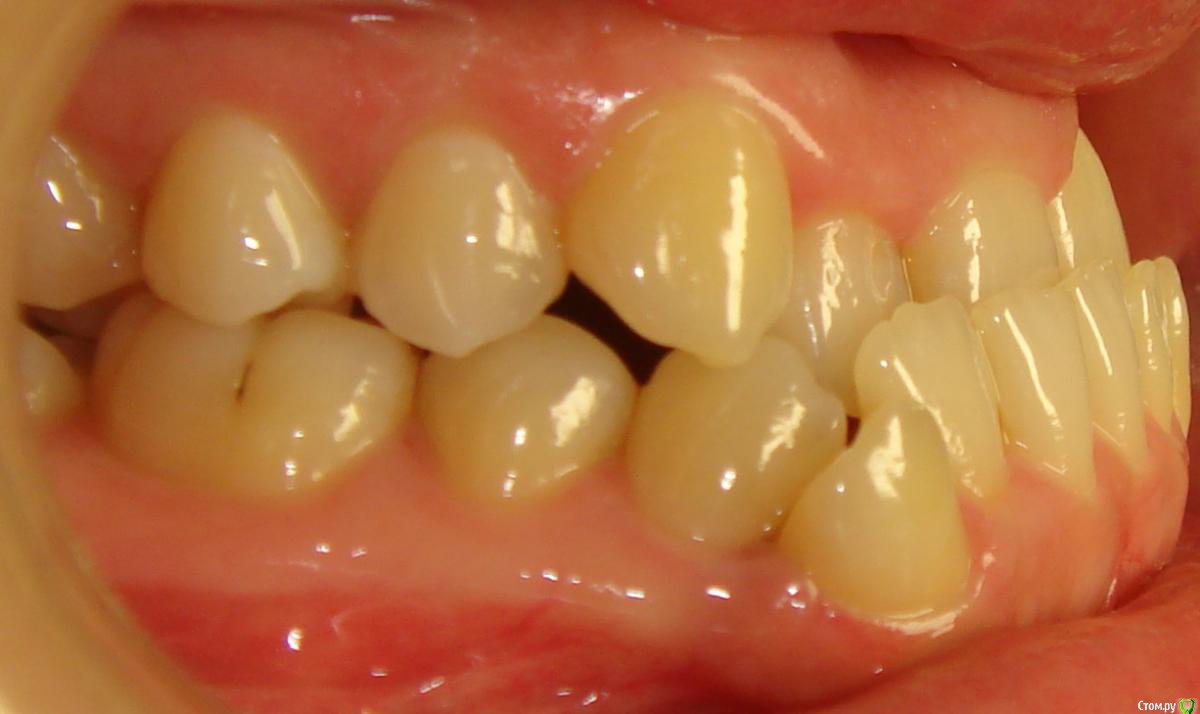

Opdihatop Опубликовано 10 декабря, 2016 Поделиться Опубликовано 10 декабря, 2016 Добрый вечер, коллеги! У меня вопрос к тем, у кого опыта по MEAW больше, чем у меня. Пациентка, 24 года, на данный момент все зубы мудрости удалены, привычная окклюзия по резцам - край в край. Сам процесс я понимаю, но есть несколько нюансов, которые хотелось бы уточнить:1) Нивелировать ли просто фронт в/ч, как книжка пишет (просто поставить дугу и все), или все-таки немного дистализировать боковые участки? С одной стороны простое нивелирование ускорит процесс и облегчит перебрасывание резцов, с другой стороны я опасаюсь чрезмерной протрузии из-за выравнивания дистопированных клыков; но при этом дистализация усугубит 3-й класс.2)Какой высоты делать окклюзионные накладки, в книжке они минимальные, а мне как то хочется побольше, чтобы резцы разомкнуть почти край в край, но не испортит ли это биомеханику?Буду очень благодарен вам за помощь! Ссылка на комментарий